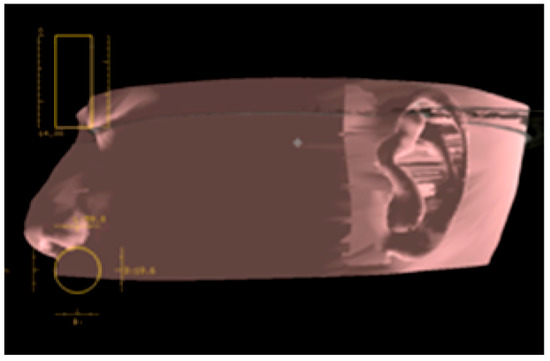

First, the CT data are obtained for use in the imaging anatomical diagnosis and simulation of the drilling positions (Figure 13). With regards to the preoperative simulation, after deciding on the location of the implant site based on the anatomical guidelines in Tjellström et al., one can use the CT images to determine if there is enough thickness to the bone to insert an implant. When planning for a navigation operation, in addition to the above, you will use the computer to create a mirror image of the unaffected ear and place this image on the affected side to get a sense of what the post-operative image may look like. For example, in the case shown in Figure 12, as a decision was already made to use the remaining elongated and deformed ear to surgically create a tragus; the mirroring of the unaffected ear helped select the section of the deformed ear that should be used as the tragus and the section that should be resected (Figure 14). Second, the surgical template with markers is fabricated; a resinous apparatus embedding two implant position markers at the drilling sites and twenty 0.5 mm metallic registration markers on the bar between the ear template and the mouthpiece fitting on the maxillary arch (Figure 15). The CT is taken again with the apparatus attached with three reflective spheres, and the registration is provided on the display (Figure 16). After the confirmation of accurate registration, the ear part of the apparatus is cut before surgery in order to let the implant positions be visible (Figure 17).

Figure 13. Preoperative implant placement simulation.

Figure 14. Using CT software, a mirror image of the healthy ear is placed on the affected ear, and the auricle resection site should be examined preoperatively.